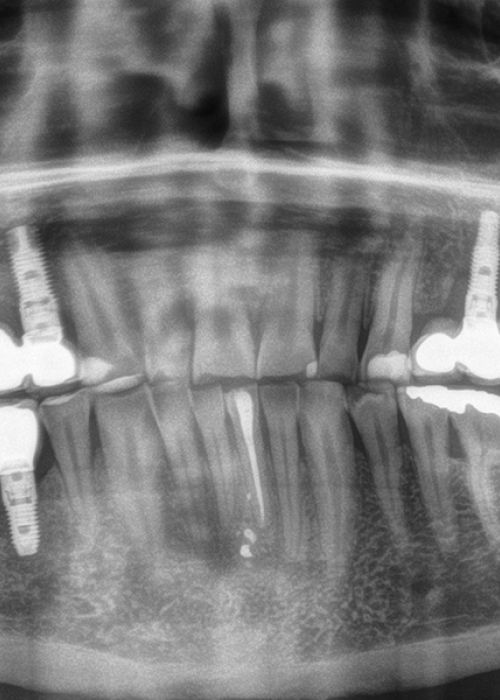

Implantes de 4,5mm de longitud utilizados en atrofia ósea en altura (hueso residual ≤ 4,5m). Estudio retrospectivo

Elevación de seno mediante abordaje transcrestal sin material de relleno con implantes extracortos (5,5 y 6,5 mm). Estudio retrospectivo con un seguimiento de 10 años

Elevación de seno transcrestal con inserción de implantes ultracortos de 4,5 mm de longitud en zonas maxilares posteriores con hueso residual menor o igual a 3 mm de altura

Implantes de 4,5 y 5,5 mm longitud insertados de forma directa en elevación crestal con hueso autólogo unido al Endoret-PRGF en alturas óseas residuales de 2-3 mm: estudio retrospectivo